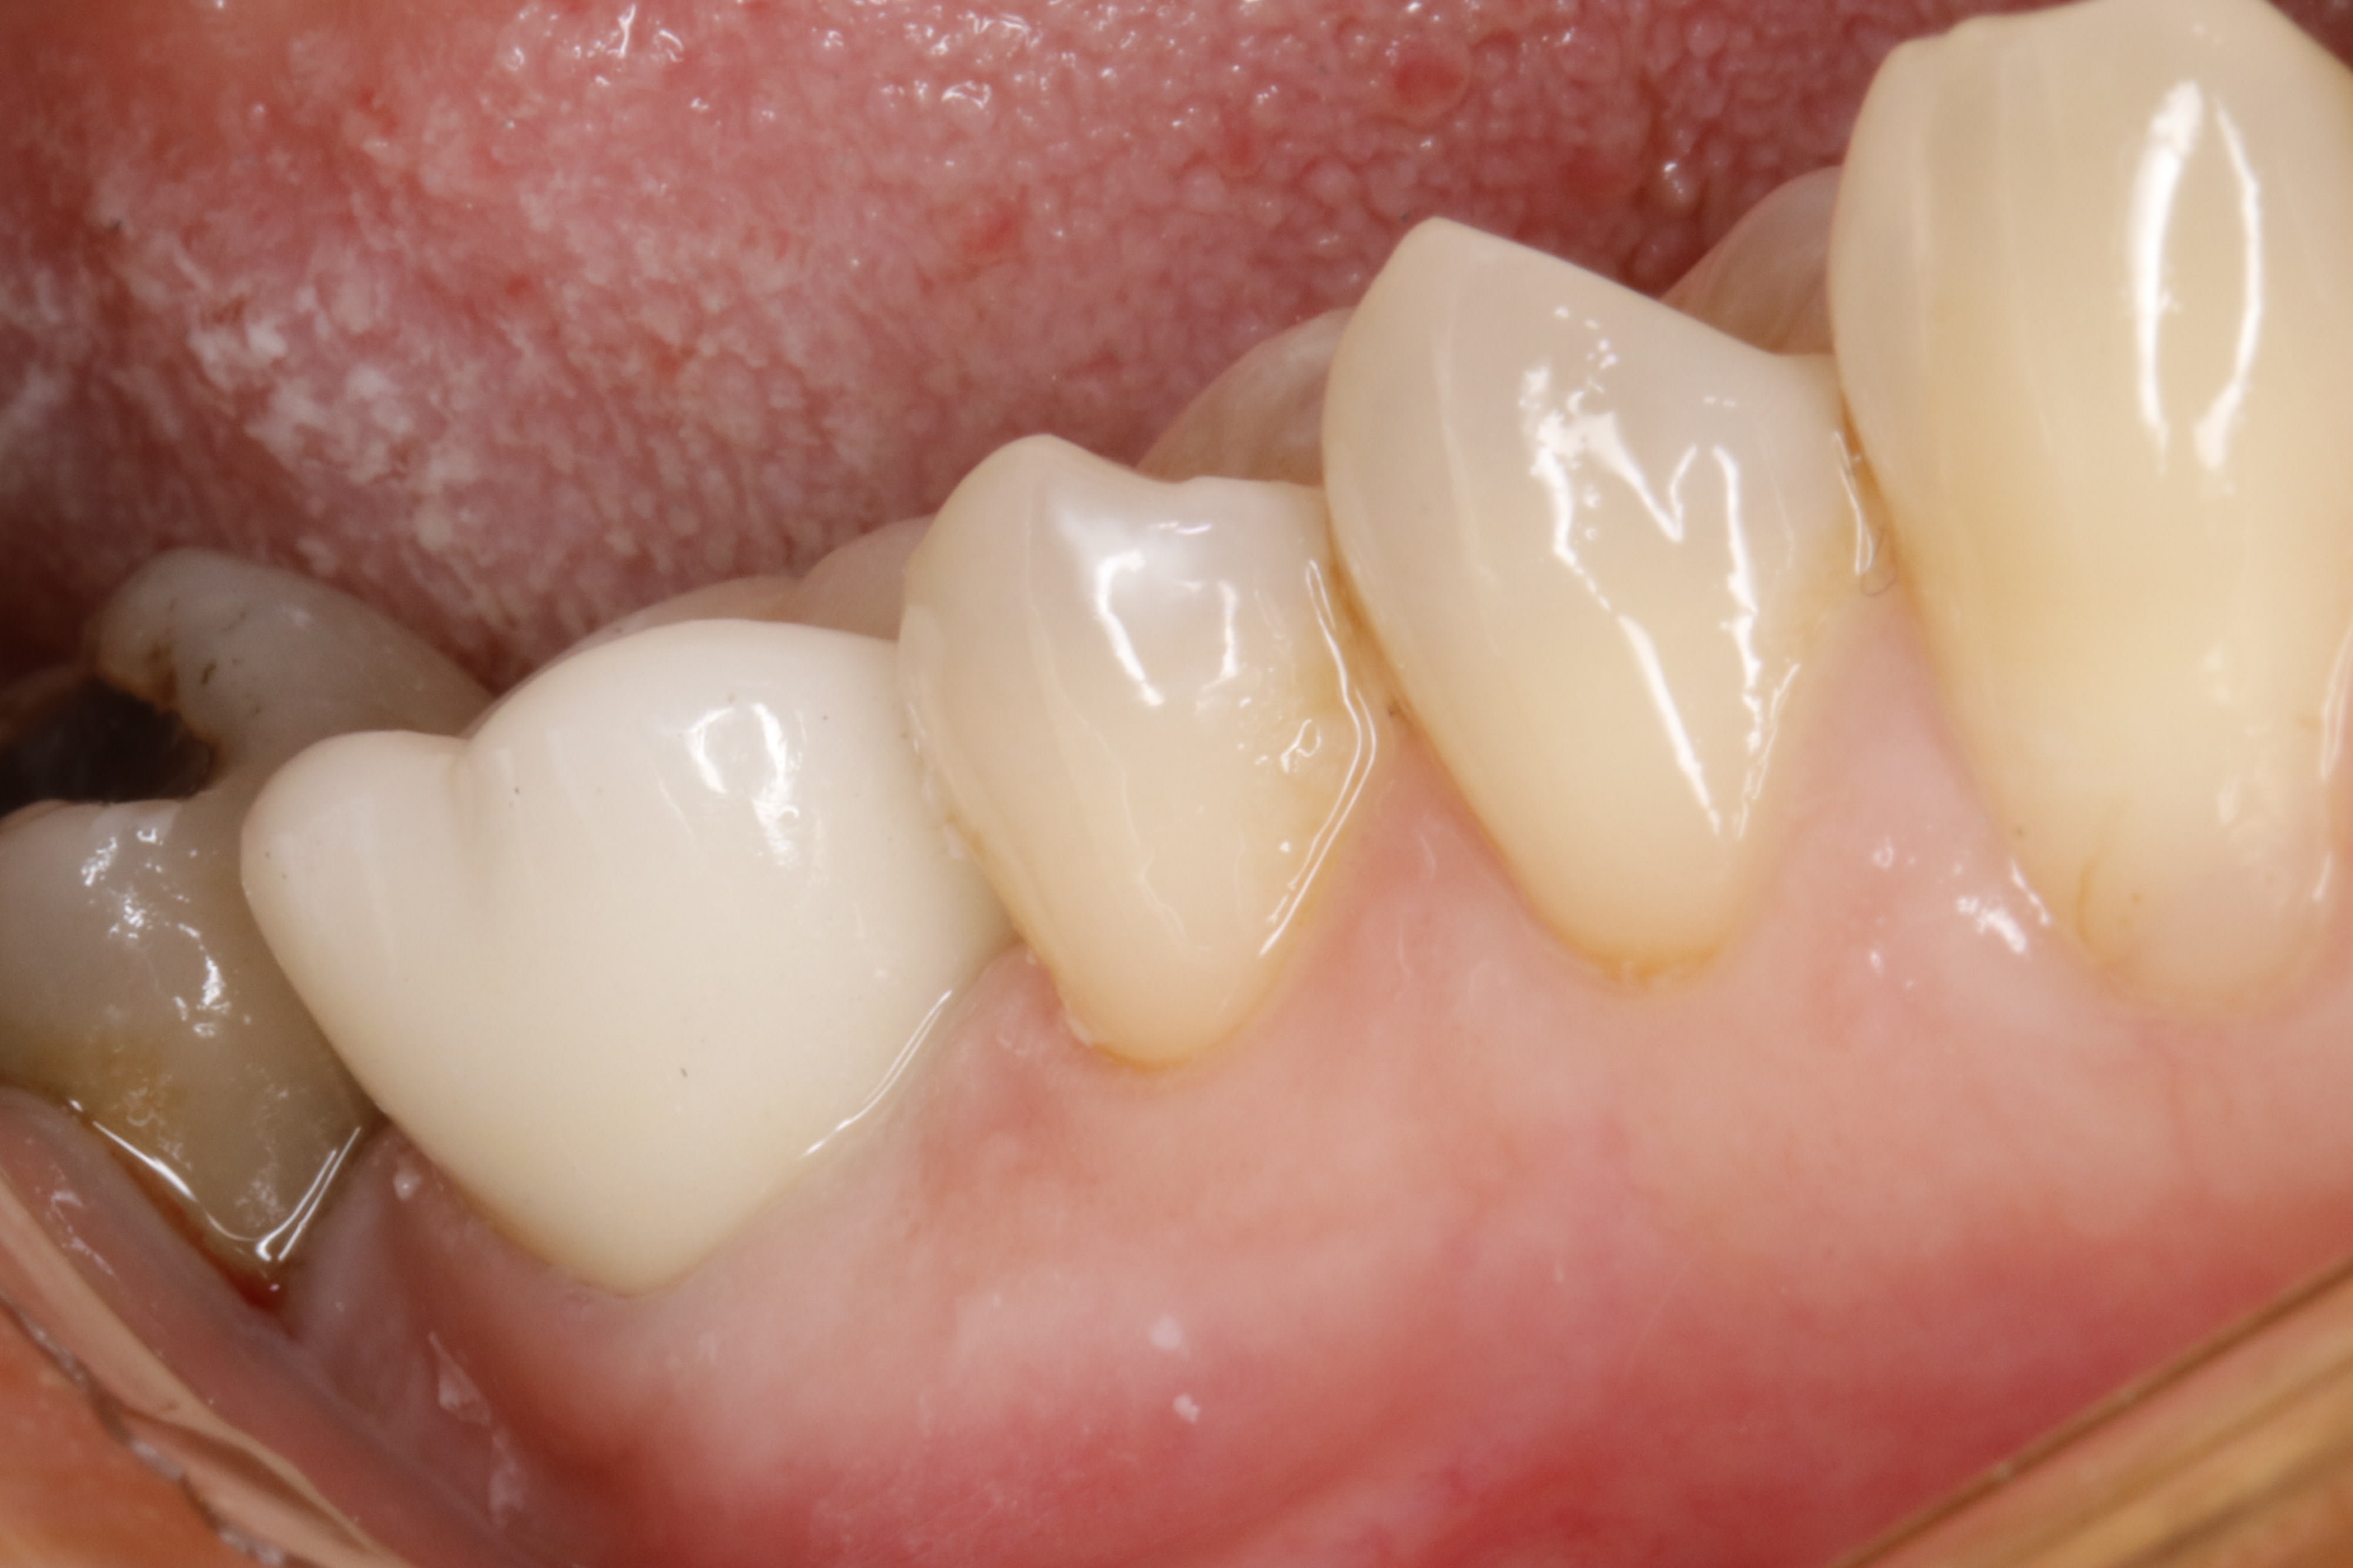

et pour finir , ç est le cas de ma 25 de la page 4 .

on a donc pris l empreinte apres avoir descendu les limites la semaine passée .

aujourd'hui , il est comme ça : la gencive a effectivement recouvert les limites , mais gentiment , tranquille .

et il suffit de sceller la ceram , et hop , on en parle plus .